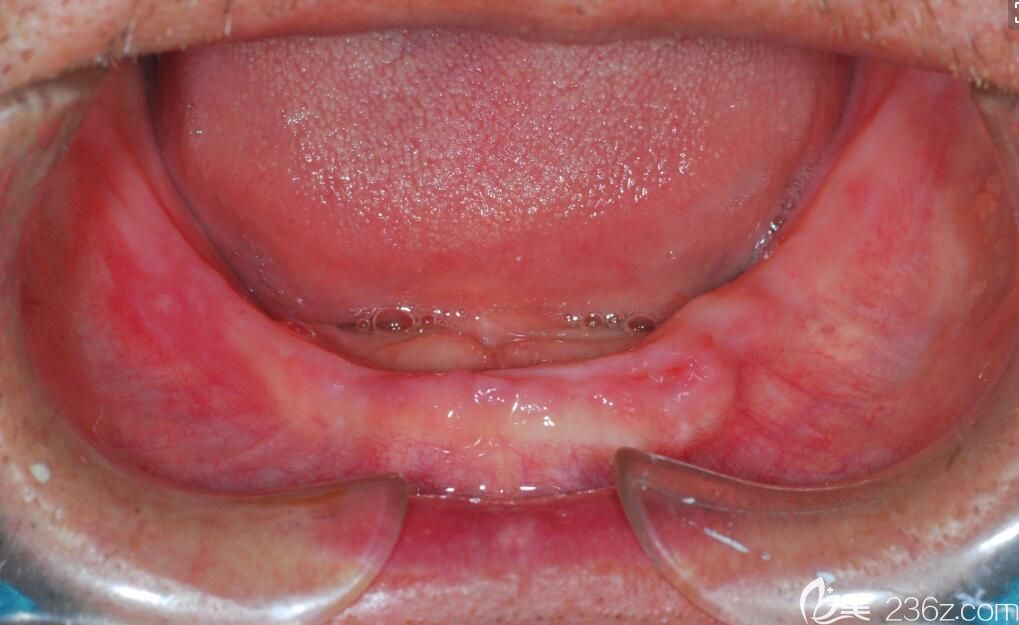

全口牙缺失,人群不僅有老年人,還有很多人年輕人,那么全口牙缺失該怎么辦呢?

黃醫(yī)生指出,年輕人牙齒缺失,醫(yī)生一般會建議他們做種植牙,因為種植牙的咀嚼和堅硬程度媲美真牙,在種植的過程中也不會傷害臨牙,并且使用時間也長,據(jù)記錄目前種植牙使用年限長的已經(jīng)超過50年了。

老年人,醫(yī)生會根據(jù)他的口腔狀況和身體狀況來判斷,他是是做種植牙,還是安裝一口活動假牙的。一般身體和口腔狀況允許,醫(yī)生也會建議老年人做種植牙。